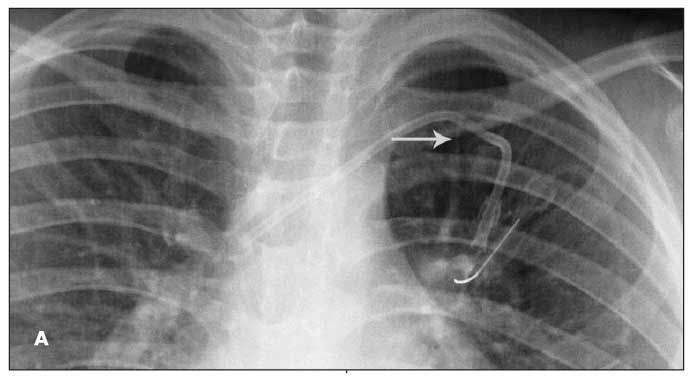

Figure A is from an 8-year-old boy with acute lymphoblastic leukemia. Fluoroscopy confirmed the catheter tip to be at the junction of the superior vena cava and right atrium with no kinks. At about month 19, during an attempt to access the CVC, the patient had pain in his left shoulder. A chest radiograph revealed a fractured piece of the CVC tubing overlying the left lung in the aortopulmonary window region. The distal fragment was lodged in the left main pulmonary artery. The patient could not recall, nor did he complain of, any traumatic events or symptoms that could be attributed to the fracture. On review of previous chest films, an intermittent focal narrowing of the catheter tubing-“pinch-off sign” (POS)-was found. The catheter fracture site (Figure A, arrow) corresponded with the area where the POS was noted.

In the first case, a POS was present in several of the patient’s chest films but was missing in others. This is probably because of the positioning of his arm. When evaluating patients with a CVC and possible intermittent POS, radiographs taken with the arms in adduction and abduction may need to be compared.10 Placing the arms in these positions at the time of insertion may also reveal sites of impingement under fluoroscopy.3 Awareness of the POS allows for replacement of the catheter, if deemed necessary, and spares the patient the risk of complications.